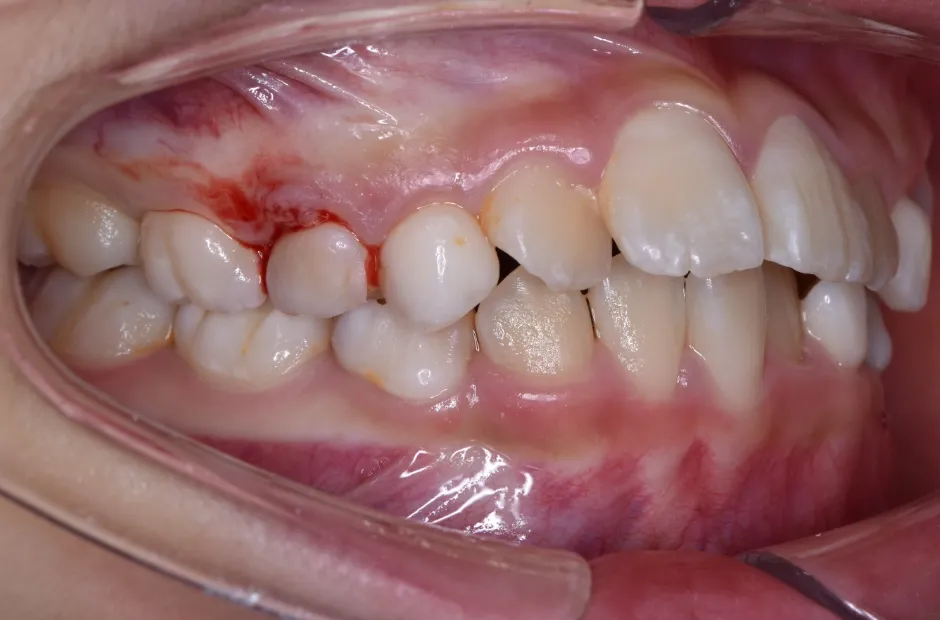

治療症例

ブラケット矯正

前歯部反対咬合

| 診断名・主訴 | 前歯部反対咬合 |

|---|---|

| 年齢・性別 | 14歳・男性 |

| 治療期間・回数 | 1年2か月 |

| 治療に用いた主な装置 | ブラケット矯正 |

| 抜歯部位 | なし |

| 治療費 | 60万円(税抜) |

| リスク・副作用 | 装置による違和感・疼痛・歯肉退縮・歯根吸収・虫歯のリスクなど |

治療中

治療前